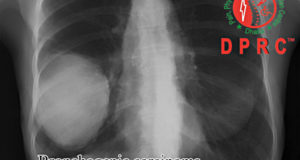

ক্যাবারনাস হেমাঞ্জিওমা কি ও চিকিৎসা

ক্যাবারনাস হেমাঞ্জিওমা বা ক্যাবারনোমাস অথবা ক্যাবারনাস মালবারসেশন একটি রোগেরই অনেকগুলো নাম।এমআরআই এর মাধ্যমে নিখুত রোগ নির্ণরকারী মেশিনের ফলে বিগত কিছু বছর যাবৎ এই রোগসমূহ আমাদের মাঝে বিরাজমান। এটি মানুষের মস্তিষ্কের অতি ক্ষুদ্র শিরা-ধমনী হতে তৈরী হয়। যেখানে শিরার সাথে ধমনির সংযোগস্থল গঠিত হয়ে থাকে। এক কথায় একে ক্যাপিলারী বলা হয়। এটি নিয়ে বিজ্ঞানীদের মাঝে এখনো তর্ক বিতর্ক চলছে যে ক্যাবারনাস হেমাঞ্জিওমা ভাস্কুলার ব্যাধী অথবা টিউমার। তবে এর বিনাইন টিউমার হবার নজির প্রচুর। এবং এর আচার আচরনও অনেক সময় তা বলে।

আশার বিষয় হলো সার্জারির মাধ্যমে সম্পূর্ণরূপে একে নির্মূল করা সম্ভব। তবে মাঝে মধ্যে সার্জারির মাধ্যমে নির্মূল করার সময় অপারেশনোত্তর কিছু পার্শ্ব প্রতিক্রিয়া দেখা যায়।